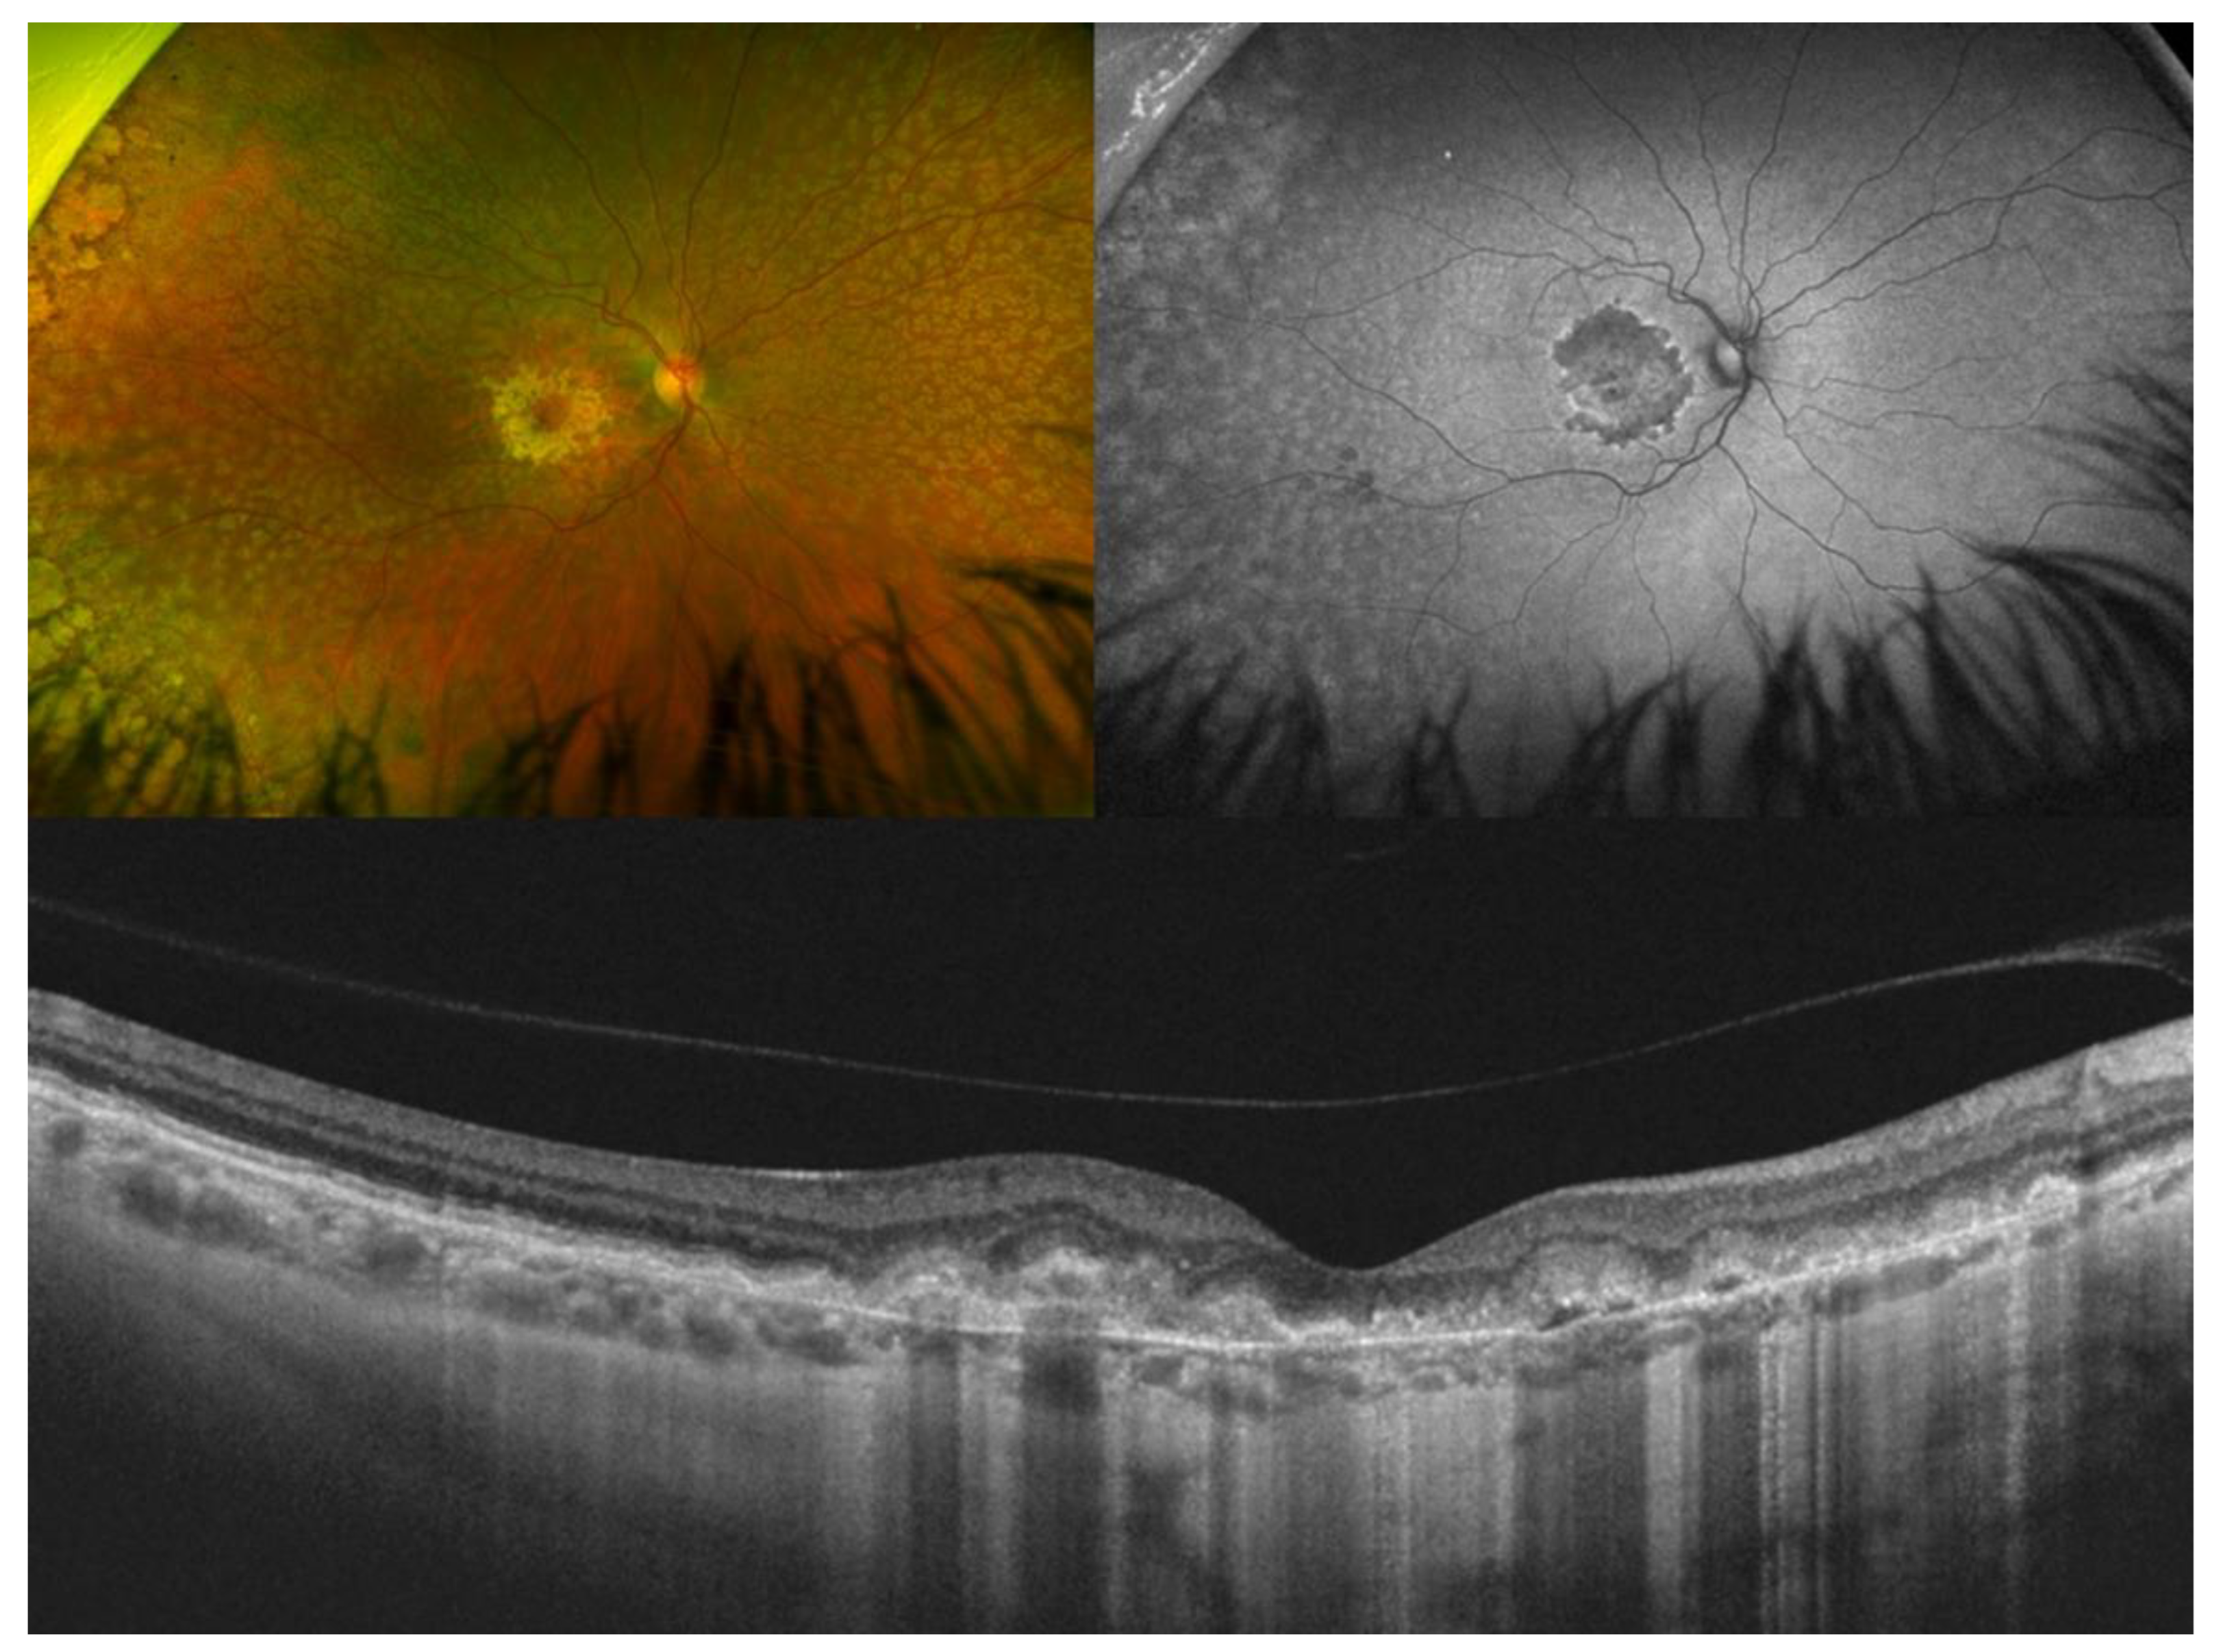

3. Best Vitelliform Macular Dystrophy

| Best vitelliform macular dystrophy |

|